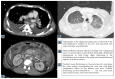

Hemophagocytic lymphohistiocytosis (HLH) is a life-threatening condition characterized by the uncontrolled activation of cytotoxic T lymphocytes, NK cells, and macrophages, resulting in an overproduction of pro-inflammatory cytokines. A primary and a secondary form are distinguished depending on whether or not it is associated with hematologic, infectious, or immune-mediated disease. Clinical manifestations include fever, splenomegaly, neurological changes, coagulopathy, hepatic dysfunction, cytopenia, hypertriglyceridemia, hyperferritinemia, and hemophagocytosis. In adults, therapy, although aggressive, is often unsuccessful. We report the case of a 41-year-old man with no apparent history of previous disease and an acute onset characterized by fever, fatigue, and weight loss. The man was from Burkina Faso and had made trips to his home country in the previous five months. On admission, leukopenia, thrombocytopenia, increased creatinine and transaminases, LDH, and CRP with a normal ESR were found. The patient also presented with hypertriglyceridemia and hyperferritinemia. An infectious or autoimmune etiology was ruled out. A total body CT scan showed bilateral pleural effusion and hilar mesenterial, abdominal, and paratracheal lymphadenopathy. Lymphoproliferative disease with HLH complication was therefore suspected. High doses of glucocorticoids were then administered. A cytologic analysis of the pleural effusion showed anaplastic lymphoma cells and bone marrow aspirate showed hemophagocytosis. An Epstein-Barr Virus (EBV) DNA load of more than 90000 copies/mL was found. Bone marrow biopsy showed a marrow localization of peripheral T lymphoma. The course was rapidly progressive until the patient died. HLH is a rare but usually fatal complication in adults of hematologic, autoimmune, and malignant diseases. Very early diagnosis and treatment are critical but not always sufficient to save patients.